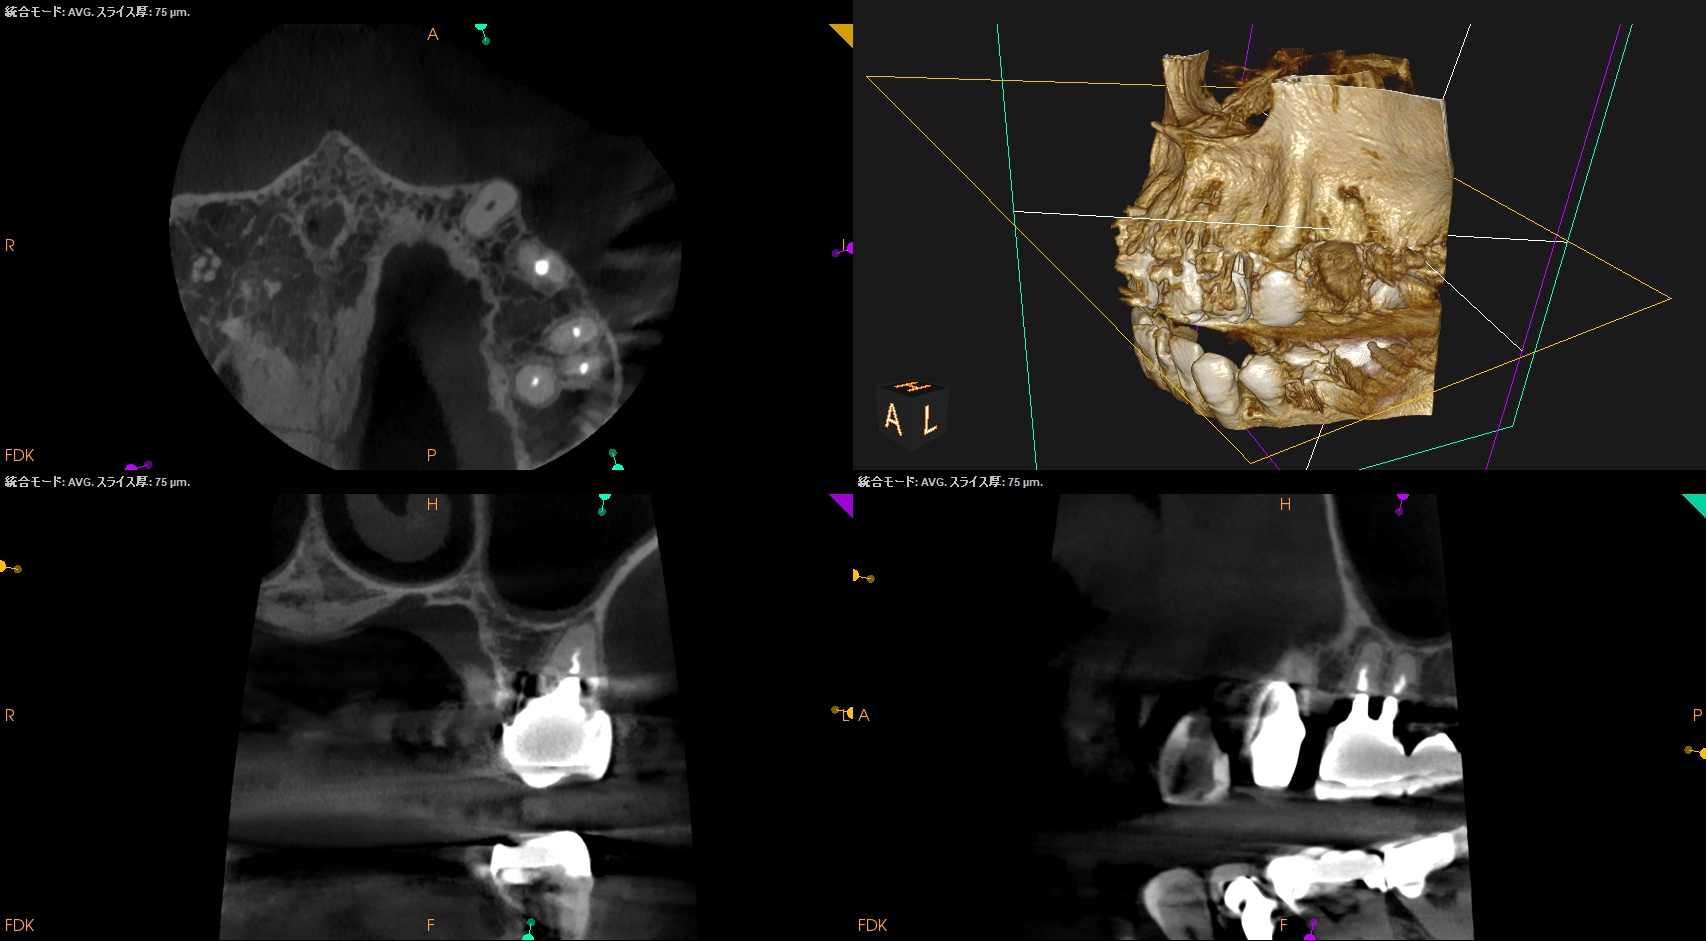

初診時+治療直後と比較した。

#3

#14

#16

劇的に病気が治癒している。

特に#16は凄まじい。

超音波洗浄しかできなかったのに根尖病変が治癒しているのだ。

免疫力が非常に強い患者さんなのだろう。